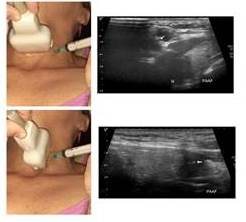

Se recomienda la utilización de agujas 22-23G y aspiración con inyectadora de 10 cm3 y bajo guía ecográfica. Se evalúa la vascularidad del nódulo a punzar. Si muestra mucha vascularidad al Doppler se realiza punción sin aspiración (por capilaridad). Se recomienda aspirar todo el contenido líquido y reservarlo para estudio citológico de centrifugado y apartarlo de la toma del componente sólido (3).